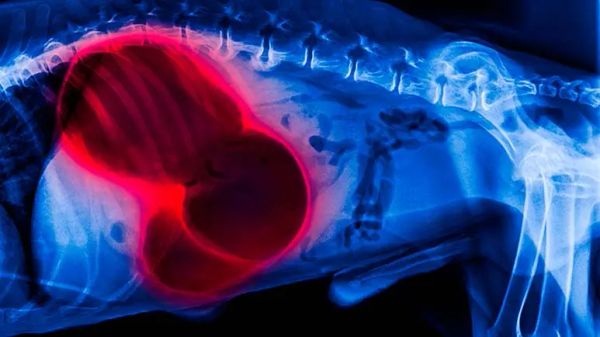

Like an Expanding Balloon in Your Pet’s Tummy, This Can Kill in Only Hours

If you overindulge, you may feel uncomfortable, but usually there's nothing to worry about. With certain dogs (especially these 12 at-risk breeds), it can be a death sentence. Know the early warning signs and solutions to help your pet on the way to the emergency clinic.